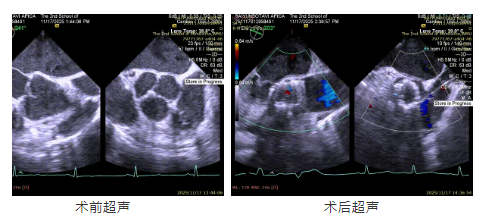

患者主動脈瓣重度反流糾正,術后無反流、無瓣周漏。術后心臟彩超顯示人工生物瓣啟閉良好,平均跨瓣壓差3mmHg,流速正常。患者恢復情況良好,心臟功能得到顯著改善。